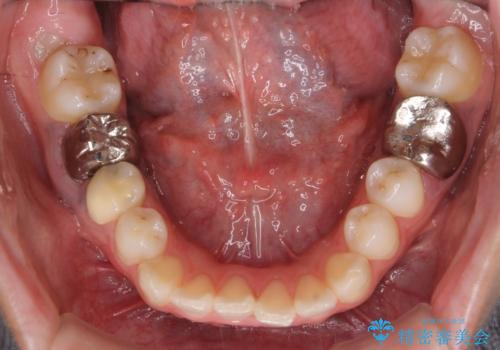

右下6番については保存不可能であり、矯正治療終了後にインプラント補綴しています。

インプラント治療については下記をご覧ください。

https://seimitsushinbi.jp/case/82835/